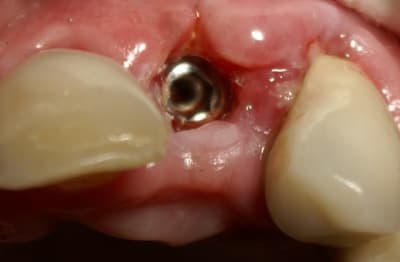

Dans ce cas là, c'était une implantation post extractionnelle immédiate et une mise en esthétique immediate.

Pour ceramik, l'implant est un Xive 3.8 dans le premier cas et un 3.4 dans le second (peut être un peu sous-dimentionné d'ailleurs).

Excellente stabilité primaire avec ces implants que je préfère aux straumann, easy et ankylos.

Tout à fait d'accord growler et c'est d'ailleurs ce que l'on peut voir sur le cas suivant. Fracture radiculaire, aucune infection periradicualire. Extraction et implantation immediate. Espace existant entre l'implant et l'alvéole est comblé par du BioOss. Un logement sous gingival est formé en vestibulaire et palatin de facon à pouvoir recouvrir le tout par BioGide et un conjonctif enfoui.

L'implant est de 15mm mais l'alvéole était large et 50% environ de la surface implantaire n'était en contact qu'avec du BioOss. J'ai pour cela préféré enfouir.

Petite question dentiste 57 : il semblerait dans le 2eme cas que tu présentes que tu ne recouvres pas ton implant par la membrane (qui pourrait comme l'a dit Amibien être poinconnée pour laisser passer ton pilier). Si c'est bien le cas peux tu m'expliquer pourquoi ? Quel est le risque à ton sens que ton comblement palatin et vestibulaire se fasse la malle par le "sulcus" entourant ton implant ?